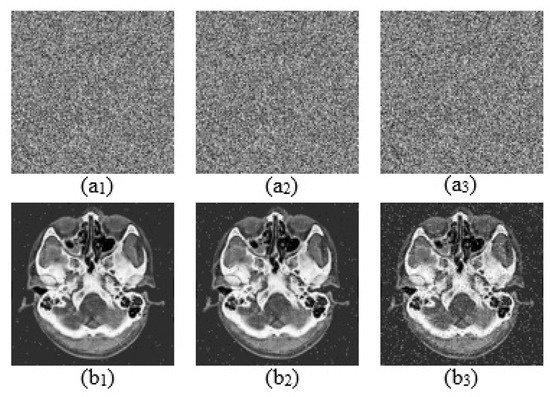

30 pages, 6264 KB

Article

An Efficient Image Encryption Scheme Based on DNA Mutations and Compression Sensing

by Jianhua Qiu, Shenli Zhu, Yu Liu, Xize Luo, Dongxin Liu, Hui Zhou, Congxu Zhu and Zheng Qin

Mathematics 2026, 14(1), 5; https://doi.org/10.3390/math14010005 - 19 Dec 2025

In communication environments with limited computing resources, securely and efficiently transmitting image data has become a challenging problem. However, most existing image data protection schemes are based on high-dimensional chaotic systems as key generators, which suffer from issues such as high algorithmic complexity [...] Read more.

In communication environments with limited computing resources, securely and efficiently transmitting image data has become a challenging problem. However, most existing image data protection schemes are based on high-dimensional chaotic systems as key generators, which suffer from issues such as high algorithmic complexity and large computational overhead. To address this, this paper presents new designs for a 1D Sine Fractional Chaotic Map (1D-SFCM) as a random sequence generator and provides mathematical proofs related to the boundedness and fixed points of this model. Furthermore, this paper improves the traditional 2D compressive sensing (2DCS) algorithm by using the newly designed 1D-SFCM map to generate a chaotic measurement matrix, which can effectively enhance the quality of image recovery and reconstruction. Moreover, referring to the principle of gene mutation in biogenetics, this paper designs an image encryption algorithm based on DNA base substitution. Finally, the security of the proposed encryption scheme and the quality of image compression and reconstruction are verified through indicators such as key space, information entropy, and Number of Pixel Change Rate (NPCR). Full article